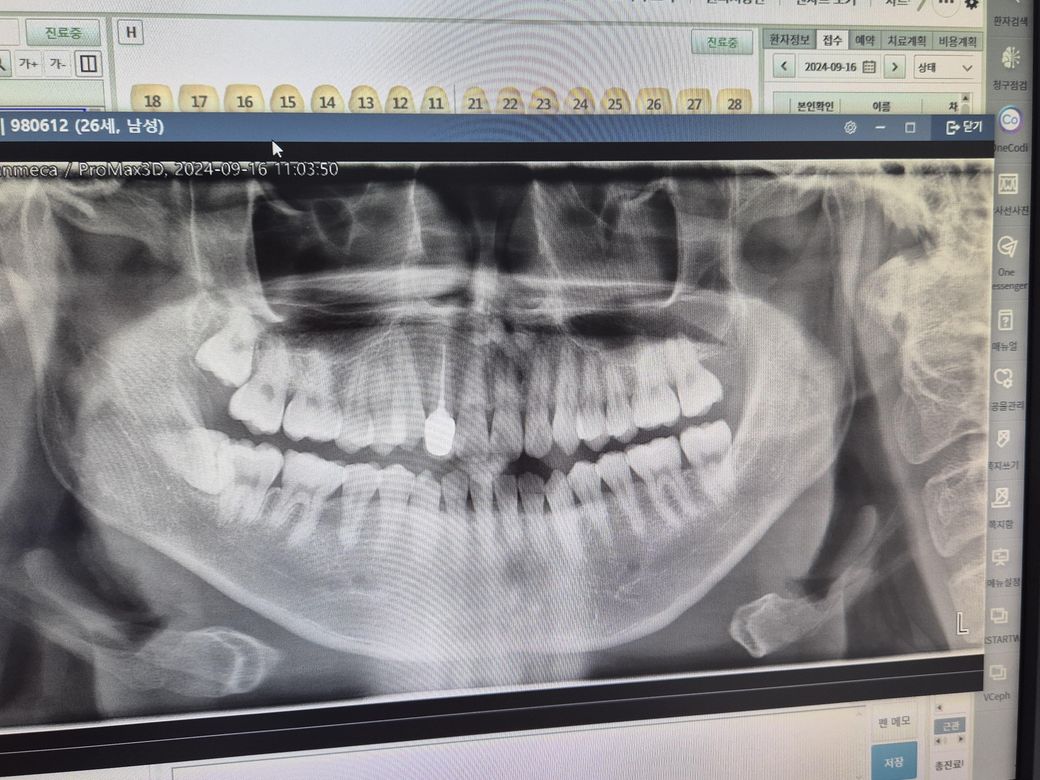

사진처럼 윗 앞니에 검은 선이 있습니다 딱히 시리다거나 그렇진 않은데 혹시 충치인가요? 위의 좌우대칭되는 치아도 신경치료 후 크라운을 씌운상태라 걱정되네요 엑스레이 사진은 9월16일 사진입니다

1. 해당치아는 엑스레이상으로 봤을때 pfm (겉은 세라믹, 안은 메탈) 크라운으로 씌워진 것으로 보입니다.

2. pfm 크라운 특징은 시간이 지남에 따라 잇몸이 퇴축되면 안쪽의 검은 메탈 부위가 드러나 치아가 검게 비쳐 보이는 것입니다.

3. 다만 지금 사진상으로는 그런 상황은 아닌 것 같고 치과에 가서 좀 더 자세히 봐야 할 것 같습니다.